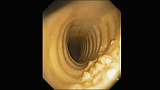

Макроскопически обнаруживаются плотные белесоватые узелки с неправильными очертаниями, выступающие над поверхностью слизистой, диаметром 1-3 мм (характерная картина «металлической тёрки»), располагающиеся исключительно в хрящевой части трахеи и никогда в мембранозной. Такая избирательная локализация патологических изменений характерна только для остеохондропластической трахеобронхопатии и не наблюдается при других заболеваниях дыхательных путей. Эти возвышающиеся узелки могут иногда сливаться в тяжи.